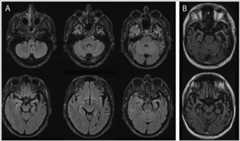

Case 5-1

A 54-year-old man presented to the psychiatric emergency department for bizarre behavior, claiming he had won the lottery. The family reported that 6 years prior to presentation he became less organized managing his finances. The family discovered 3 years ago that bills, including the mortgage, were going unpaid, and he had accumulated significant credit card debt. His affect became flat and his family reported that it was “hard to get a reaction out of him.” He began to cook in an impulsive way, turning the burners on maximum for everything. The patient had lost his job for inappropriate borrowing of money from clients 1 year prior to presentation. He began buying multiple lottery tickets each week, and despite financial difficulties, he purchased a luxury motorcycle. He began wearing the same clothing multiple days in a row and required encouragement to shower. He lost interest in his hobbies and spent increasing amounts of time “staring” at the television. Family history was negative for any neurodegenerative diseases, although his father died in his forties of a myocardial infarction, and his mother died in her early sixties of cancer. On examination, the patient was mildly unkempt, with a flat affect, and appeared apathetic. His speech was fluent with preserved naming, repetition, and comprehension. Cranial nerves were intact, including normal saccades. There was no evidence of bradykinesia. Sensory and motor examinations were normal. He had mild difficulty performing the Luria hand sequence (a three-step hand movement sequence of fist-side-flat) on the left compared to the right. Snout and grasp reflexes were absent (normal). On cognitive testing, he scored 26 out of 30 on the Mini-Mental State Examination (MMSE) and 14 out of 30 on the Montreal Cognitive Assessment (MoCA), losing points for attention, concentration, working memory items, and Trail Making B test sample. Semantic and phonemic fluency were both moderately impaired. MRI imaging demonstrated bifrontal and temporal atrophy (Figure 5-1). Subsequent genetic testing forC9ORF72,GRN, andMAPT did not reveal any pathogenic mutations. A diagnosis of probable behavioral variant of frontotemporal dementia (FTD) was made. He was advised to stop driving and was reported to the Department of Transportation. Family were referred to a social worker and an FTD caregiver support group. Citalopram 20 mg/d was started with modest improvement of the obsessive behaviors.

Figure 5-1.

T2-weighted axial MRI shows bifrontal and temporal atrophy in the patient inCase 5-1 with sporadic behavioral variant of frontotemporal dementia.